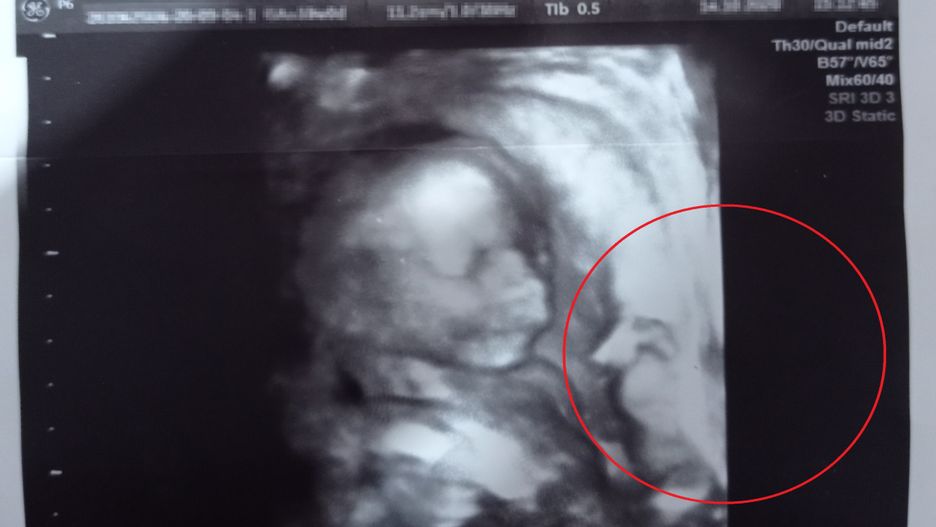

Czytelniczka o2.pl podzieliła się z redakcją swoim zdjęciem z USG ciąży. Powód? Gdy przyjrzała się fotografii uważnie, okazało się, że widnieje na nim nie tylko twarz jeszcze nienarodzonego dziecka. Czy to mógł być anioł stróż?

Jak relacjonowała pani Aneta, nadesłane zdjęcie z USG przedstawia jej synka. Chłopiec przyszedł na świat zaledwie kilka miesięcy temu, bo 21 marca, o godzinie 21:00.

Jak wyznała pani Aneta, wierzy, że jej samej w trakcie ciąży przytrafiła się podobna historia, co bohaterce artykułu. Zdjęcie na którym – według czytelniczki o2.pl – widać anioła stróża malucha, zostało wykonane w połowie października ubiegłego roku.

Na zdjęciu USG wyraźnie widać... dwie twarze. Jednak przyszła mama wcale nie spodziewała się bliźniąt

Chciałam się podzielić naszym zdjęcie, ponieważ był to dla nas szok – nasz synek, który się urodził w tym roku 21 marca o 21, też ma anioła stróża na USG – relacjonowała pani Aneta w rozmowie z o2.pl.

Trudno jednoznacznie rozstrzygnąć, w jaki sposób na zdjęciu z USG pojawiła się przypominająca ducha postać. Osoby sceptycznie tłumaczą taką obecność złudzeniem optycznym, a wierzące – uważają, że to znak, że jeszcze przed narodzinami nad dzieckiem czuwa anioł stróż.